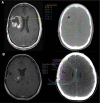

Results: We identified 64 cases of mostly (80%) biopsy-confirmed PP (n = 27) and TN (n = 37), comprising 137 ROIs in total V体育ios版. Median time of onset for PP and TN was 1 and 11 months after RT, respectively. Clinically, PP occurred more frequently during active antineoplastic treatment, necessitated more steroid-based interventions, and was associated with glioblastoma (81 vs. 40%), fewer IDH1 mutations, and shorter median overall survival. Radiographically, TN lesions often initially manifested periventricularly (n = 22/37; 60%), were more numerous (median, 2 vs. 1 ROIs), and contained fewer malignant elements upon biopsy. By contrast, PP predominantly developed around the tumor resection cavity as a non-nodular, ring-like enhancing structure. Both PP and TN lesions almost exclusively developed in the main prior radiation field. Presence of either condition appeared to be associated with above-average overall survival. .

Conclusion: PP and TN occur in clinically distinct patient populations and exhibit differences in spatial radiographic pattern. Increased familiarity with both conditions and their unique features will improve patient management and may avoid unnecessary surgical procedures. VSports最新版本.